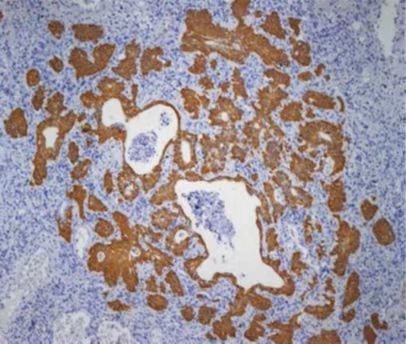

图2 支气管基底层细胞在人肺损伤区域增殖